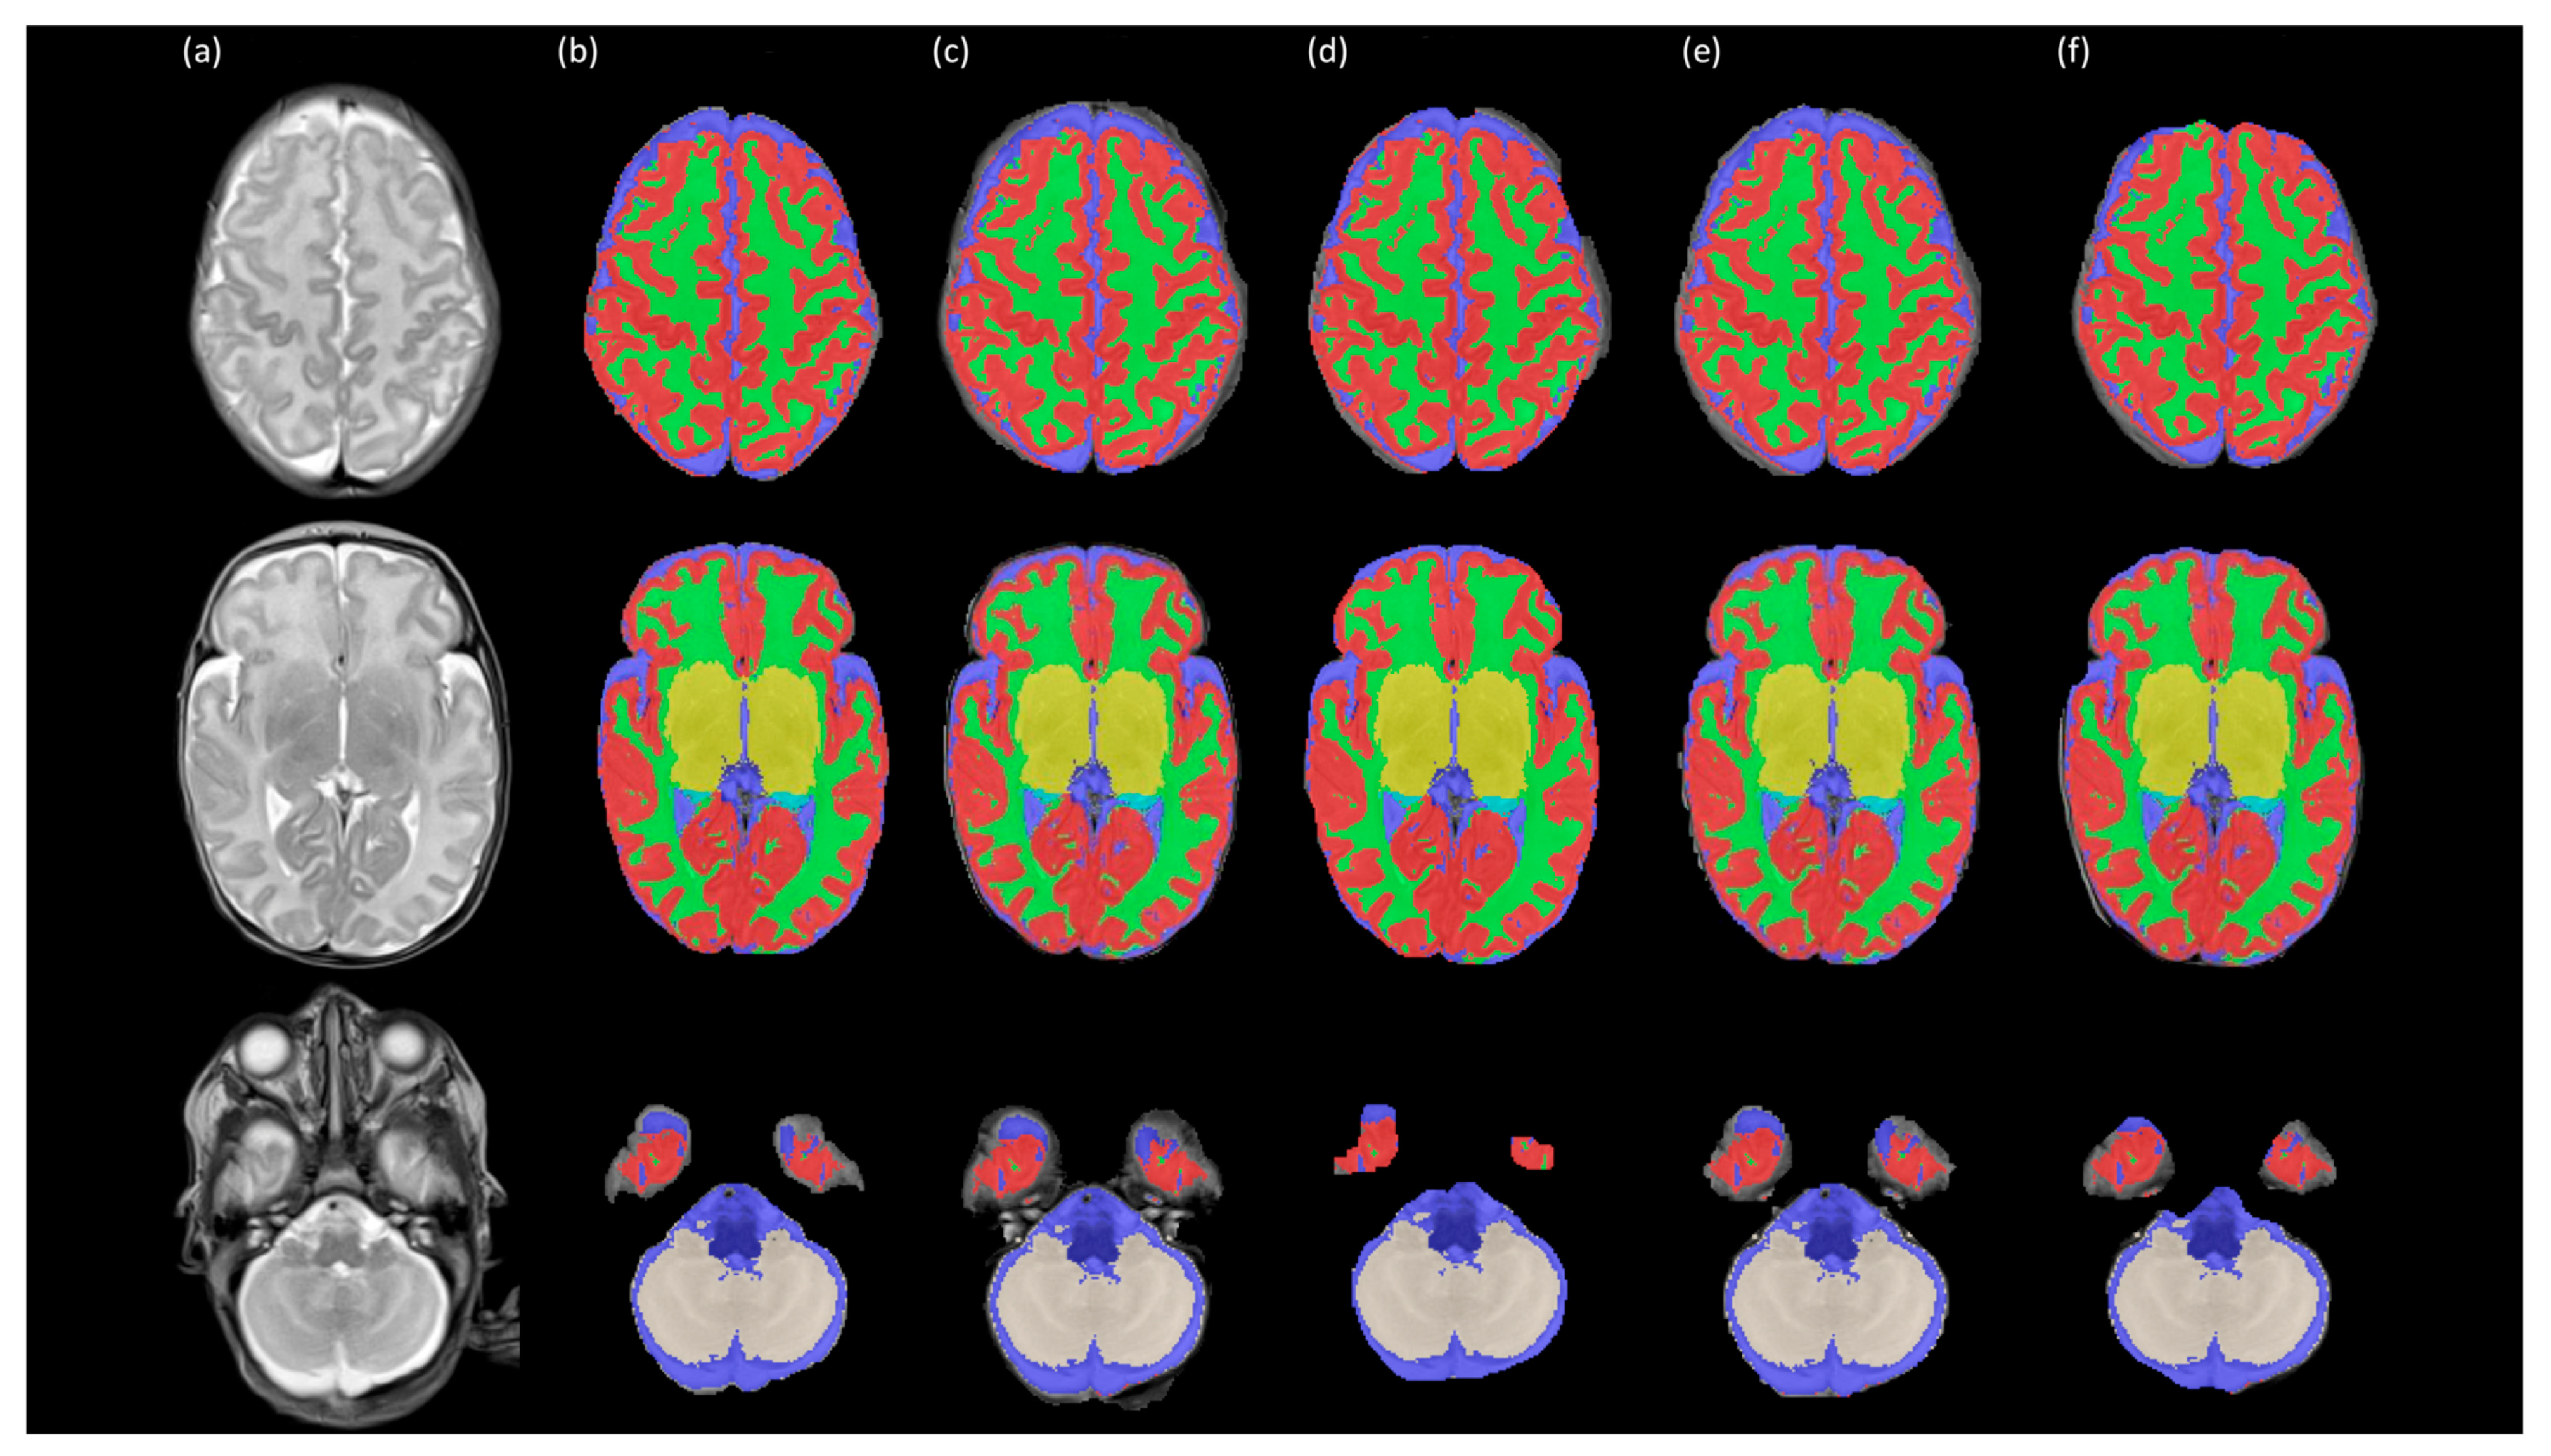

3.1. Assessment of Intensity Variability and Segmentation Performance

3.2. Assessment of Regional Brain Volume Measurements After Different Preprocessing Steps

3.2.1. Comparison Between Bias Field Correction Methods

3.2.2. Comparison Amongst Brain Extraction Methods